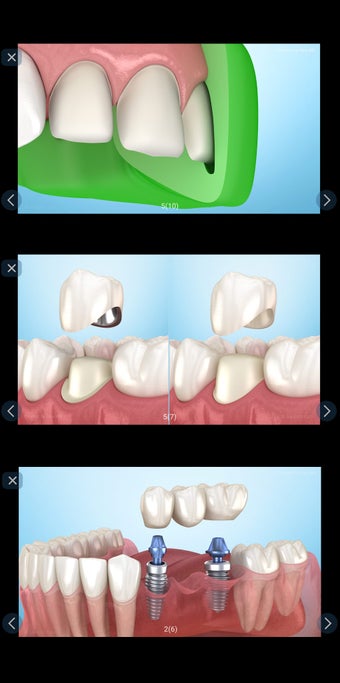

إذا كنت متخصصًا في طب الأسنان أو مريضًا، فقد تساعدك هذه الأداة في تعلم علاجات الأسنان.

تم إنشاء هذا التطبيق بواسطة أليكس ميت للأطباء الأسنان وطلاب طب الأسنان والمرضى. كما يمكن استخدامه أيضًا من قبل المهنيين الطبيين الآخرين.

يستند التطبيق على مبدأ عرض الشرائح. يحتوي كل موضوع على 3-9 صور. يمكن عرض صور أي موضوع في أي وقت.